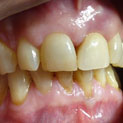

En estos casos han sido tratados con la filosofía de all-at-once, en la

misma sesión: